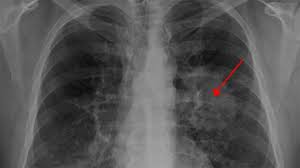

This mass will look like a white spot on your lungs, while the lung itself will appear black. Advanced genomic testing looks for dna alterations in cancer cells that may be driving the growth of tumor. With a ct scan, the machine. The computer puts them together to make a 3 dimensional (3d) image. A ct scan can help doctors find cancer and show things like a tumor's shape and size.

A ct scan can detect potential cancer in a lung.

Sometimes a ct scan or mri scan is all that is needed to make a diagnosis of secondary cancer in the lymph nodes. This shows the cancer more clearly. Ct (or cat) stands for computed (axial) tomography. Advanced genomic testing looks for dna alterations in cancer cells that may be driving the growth of tumor. I had to drink the contrast dye stuff before it and also had the other dye which went in intravenously. The doctor will then order additional testing to rule out or confirm a cancer diagnosis. In some cases, a medical practitioner may inject a contrast medium to highlight certain structures within the breast. Would a pancreas ct with contrast rule out cancer?had urq, ulq & back discomfort for 6 weeks. The ct scanner used for my scans was an open device that looked much like the one pictured above.however, other cat scan machines are bigger contraptions that automatically move you into a long, narrow tunnel. It also helps doctors predict how well you will recover.find the right place for a biopsy.plan This mass will look like a white spot on your lungs, while the lung itself will appear black. The person lies on a table that moves through a scanning ring, which looks like a large doughnut. The diagnostic algorithm for lung cancer screening is evolving.